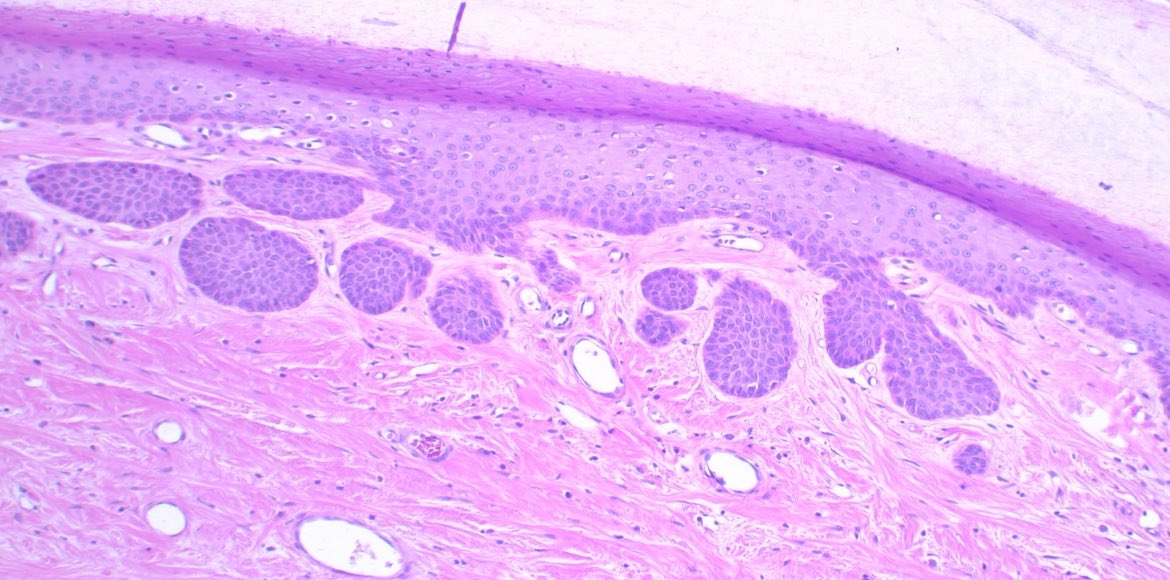

Primary Cutaneous Anaplastic Large Cell Lymphoma With TCR‐γδ Expression: A Case Series 👇👇👇 Grateful to the ASDP Mentorship Award for funding our project. It opened my eyes to horizons I never imagined in CTCL and my dermPath. #dermpath #CTCL #hemepath American Society of Dermatopathology USCLC